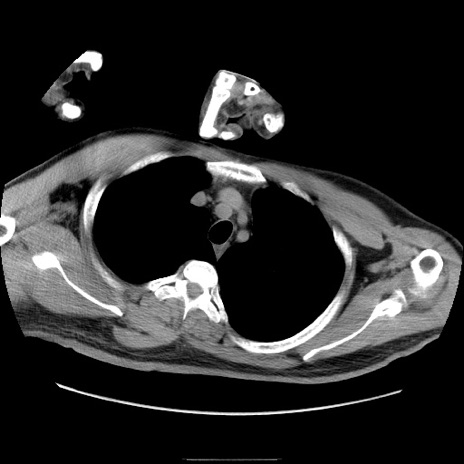

症例22(横断像)

【症例】50歳代男性

【主訴】腹痛

【現病歴】AVMからの被殻出血のため回復期リハ病棟入院中。 本日午後3時頃急に下腹部痛が出現した。

【既往歴】AVM、被殻出血、虫垂炎、高血圧

【身体所見】意識晴明、左半身不全麻痺、会話の理解は良好、36.5°C、腹部:膨隆、全体に板状硬、下腹部正中に圧痛点あり、反跳痛-、筋性防御不明、右下腹部にope scar

【データ】WBC 9400、CRP 0.06